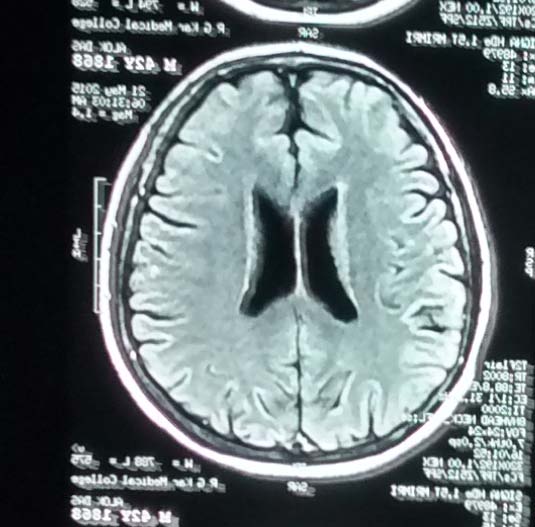

In addition to the ESS scores of the patients, all patients were evaluated for recovery using single photon emission computerized tomography (SPECT) scan and magnetic resonance imaging (MRI). At the end of therapy (T6) most patients showed improved perfusion on SPECT scan. (

The present study has shown promising results among the patients with CVA after treatment with hESC therapy. Most of the patients included had difficulty in maintaining leg position, leg flexion, gait, arm outstretched position, raising of arms and fingers, foot dorsiflexion, wrist extension, and experienced difficulty in speech. However, these patients demonstrated an improvement in their condition after receiving hESC therapy. After receiving hESC therapy, an improvement by at least one level was noted in gait (22 patients); speech (15 patients); level of consciousness (2 patients); comprehension and gaze (1 patient each),. Improvement in these parameters showed a better QoL among most patients included in the present study. The patients who received hESC therapy at the early stages of CVA showed a better improvement in most aspects as compared with patients who received hESC therapy at later stages of CVA. SPECT scan done after the therapy showed normal perfusion as compared with SPECT scan done before the therapy. (Figure 2

There are very few studies which have shown the effect of hESCs in the treatment of stroke. The difficulty in isolation of hESCs has restricted evaluation of their potential in the treatment of CVA. After being transplanted, hESCs grow in the affected area to replace the degenerated cell type. hESCs regenerate damaged cells by communicating with the damaged area and "homing" in the site of injury. This often occurs by the release of chemokines, cytokines, and growth factors from the site of injury [25]. In addition, the route of administration was selected as this shows an impact on the migration of hESCs and their ability to "home" in the damaged tissue. MSCs have also shown the influence of administration route on their potential to migrate and home at the site of injury [26]. The route of administration and the dosing schedule of hESCs play a vital role in their mechanism of action. The IM and IV routes were used to facilitate faster migration and transplantation of the hESCs to the affected area. A gap phase was included between each treatment period to facilitate the process of homing, and regeneration within the body. Adequate time intervals were maintained between each treatment period for the elucidation of maximum effect in the affected areas of the brain. Patients were treated in subsequent treatment phases after carefully monitoring the extent of improvement with MRI and SPECT scan. In the present study, we used hESCs which were isolated using a patented in-house technique for the treatment of patients (United States Granted Patent-WO 2007/141657A PCT/1B 2007 Published 13 Dec 2007). These cells do not have any xeno-product in them.